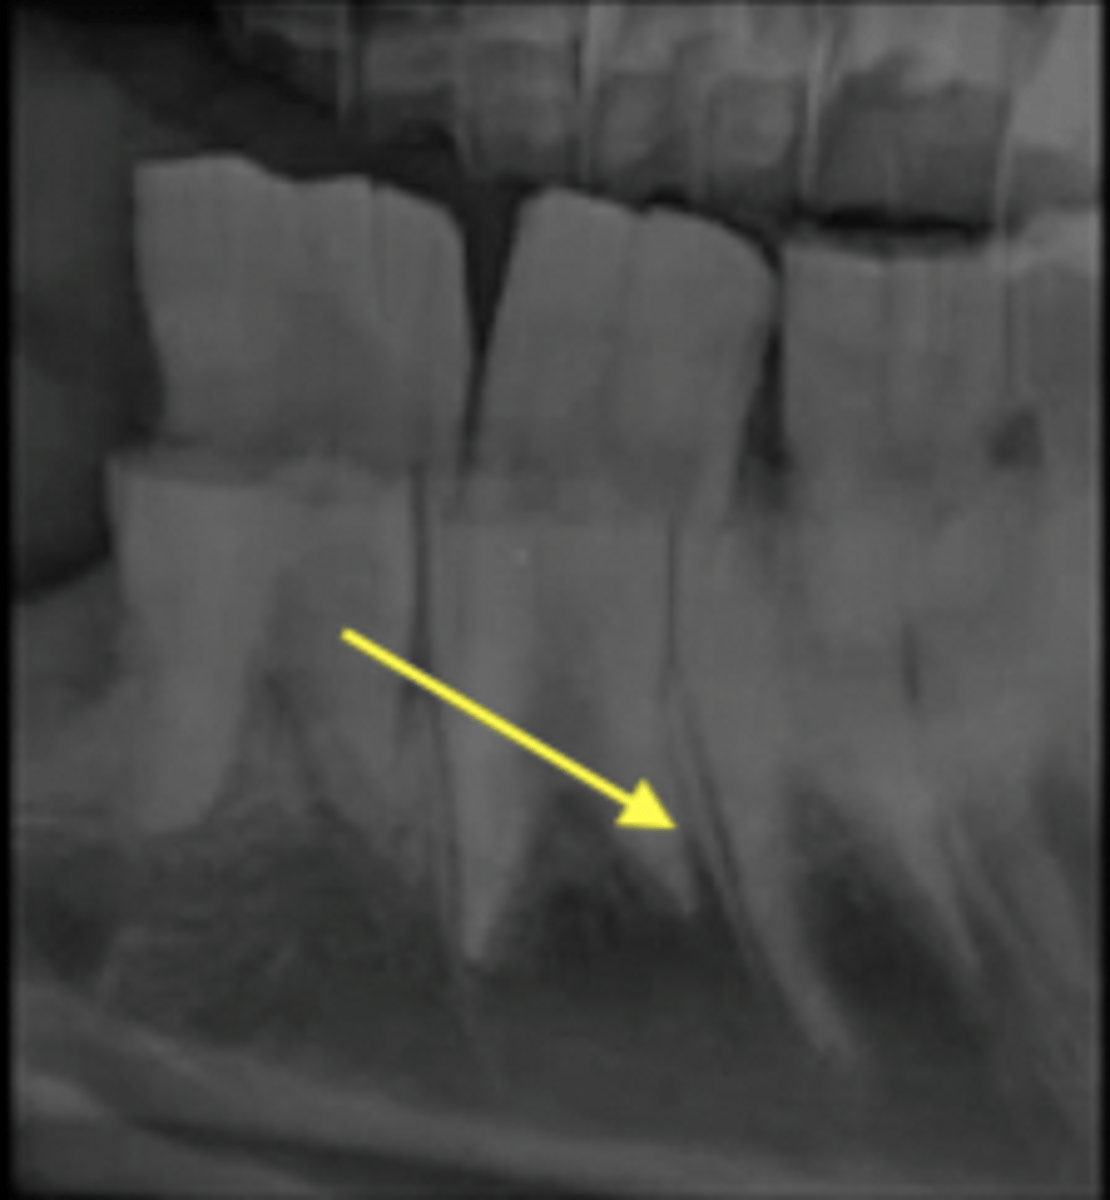

sutures of skill, periodontal ligament of the teeth

Examples of fibrous joints

fibrous

What type of joint is pictured?